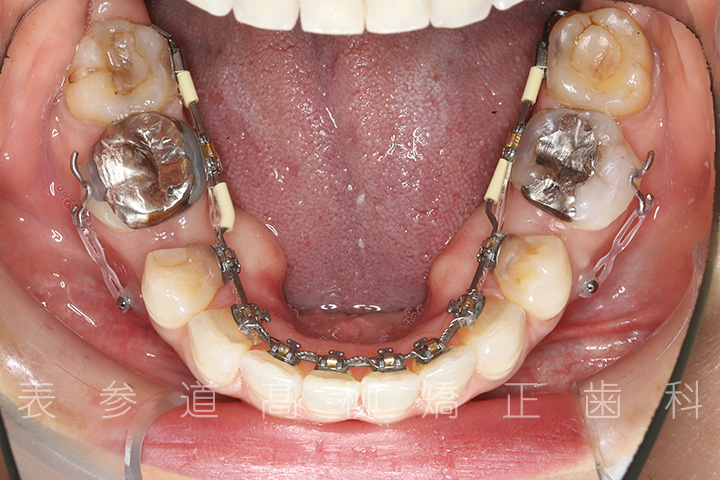

・リンガルブラケット装置

・歯科矯正用アンカースクリュー(i-station)

・マウスピース型矯正装置

・歯科矯正用アンカースクリューを併用し、下顎大臼歯の近心移動(前方への移動)

・上下歯列の緊密な咬合関係の確立に顎間ゴムを併用(装着時間20時間以上/日)